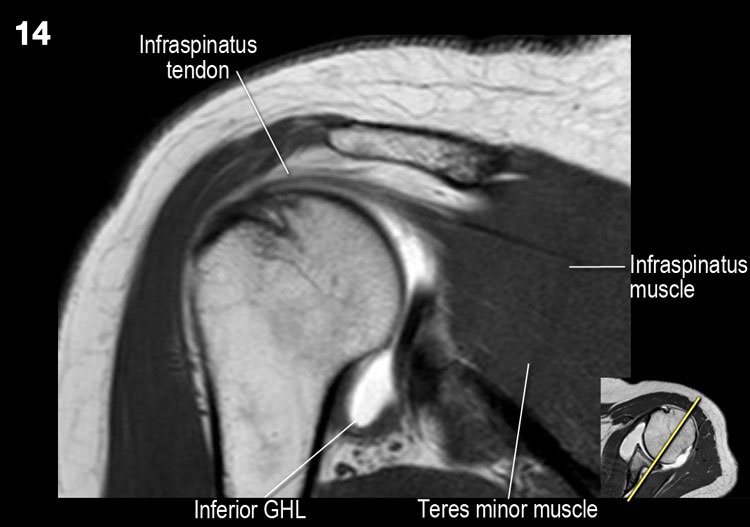

Hình ảnh mặt sau

Hình ảnh thể hiện các cơ và gân của cơ trên gai, cơ dưới gai và cơ tròn bé. Tất cả đều bám vào mấu động lớn.

Giải phẫu mặt cắt đứng dọc và danh sách kiểm tra

- Lưu ý các cơ chóp xoay và tìm kiếm dấu hiệu teo cơ.

- Gân cơ dưới gai và cơ tròn bé